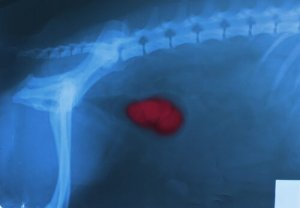

Kidney stones

Kidney stones appear when there are high levels of substances such as calcium, oxalate, or uric acid in the body that the kidneys are unable to get rid of. These substances gradually build up, forming crystals. The crystals can lodge themselves in any part of the urinary tract, from the kidneys to the bladder. They damage the internal lining, causing bleeding.